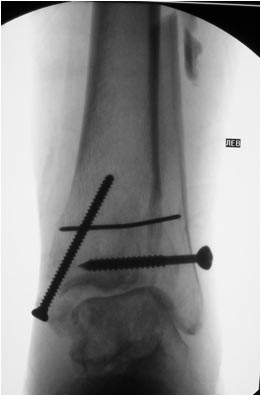

Оперировал эту пациентку 23 лет 11 лет назад через 8 месяцев после

похожего на представленный Вами остеосинтез. На первой операции перелом

малоберцовой кости в нижней трети был просто не замечен. За счет

восстановления оси быстро развившийся артроз протекал благоприятно. В

результате артродез был выполнен только в прошлом году, через 10 лет

после второй операции. И боли беспокоили пациентку только в течение года

перед артродезом.